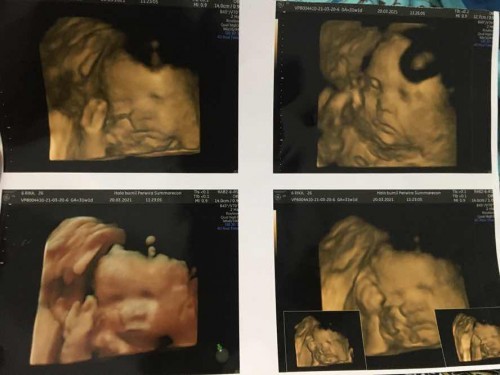

Mohon maaf cuma mau mengungkapkan kebahagiaan ya bunda2 🙏🏻 Subhanallah bahagia nya skrg usia dede di dlm kandungan ibun sudah 21minggu. Gasabar ayah sama ibun mau ketemu kamu. Gerak yg aktif ya nak 😘😘😘 Kalo sudah waktunya lahir kedunia segera ya nak disini ada ayah dan ibun 🥰 #pregnancy #firstbaby #jangandibully